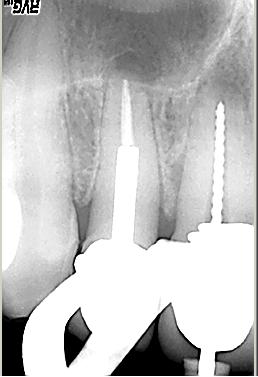

Abschlusskontrolle der WF

Abschlusskontrolle der WF im Oktober 2002. Man beachte die dreidimensionale Füllung des apikalen Deltas des distalen Kanalsystems (hier konnte Patency etabliert werden) sowie die Füllung der Seitenkanäle im Bereich der Furkation, auf deren Höhe sich auch der lingualen Abszeß befand.